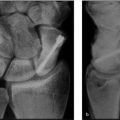

Carefully plan the location, angle, and direction of osteotomy to achieve desired correction

Achieve rigid stable fixation of osteosynthesis site, to prevent recurrence of deformity

Anticipate need for bone graft to augment stability and/or cellularity of osteosynthesis site

Perform frequent re-assessment of correction intraoperatively to ensure patient’s goals are achieved